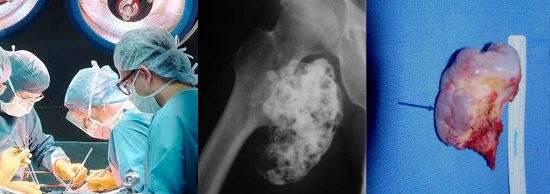

Хирургическое удаление остеохондромы проводится под общим наркозом. Врач делает надрез кожи в области опухоли и выполняет краевую резекцию, удаляя новообразование вместе с основанием. В большинстве случаев дополнительная костная пластика не требуется. После операции пациенты, как правило, быстро восстанавливаются, и вмешательство приводит к стойкому выздоровлению, при этом остеохондрома не возникает повторно.

Внимание! Видео операции. Рекомендуется избегать просмотра детям до 18 лет, беременным и людям с нестабильным психическим состоянием.